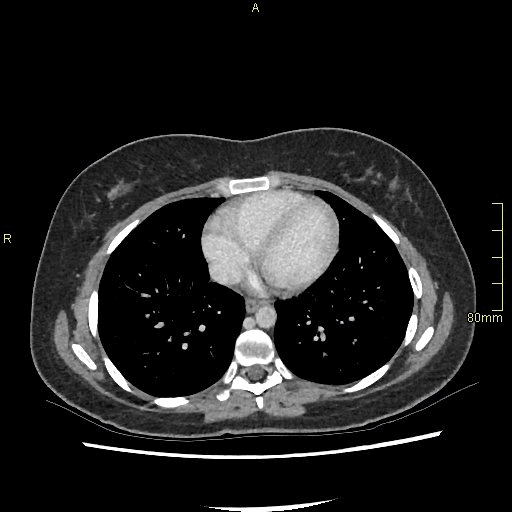

For patients over the age of 40, a non contrast KUB, and seperate nephrogenic and excretory (delayed) phases will be performed. For all patients under the age of 40, a non contrast KUB and a COMBINED dual nephrogenic/excretory phase will be performed. Image examples of this can be seen below.

Under 40 Years of Age

CT Urogram- Nephrogenic + Excretory Phase (Axial)